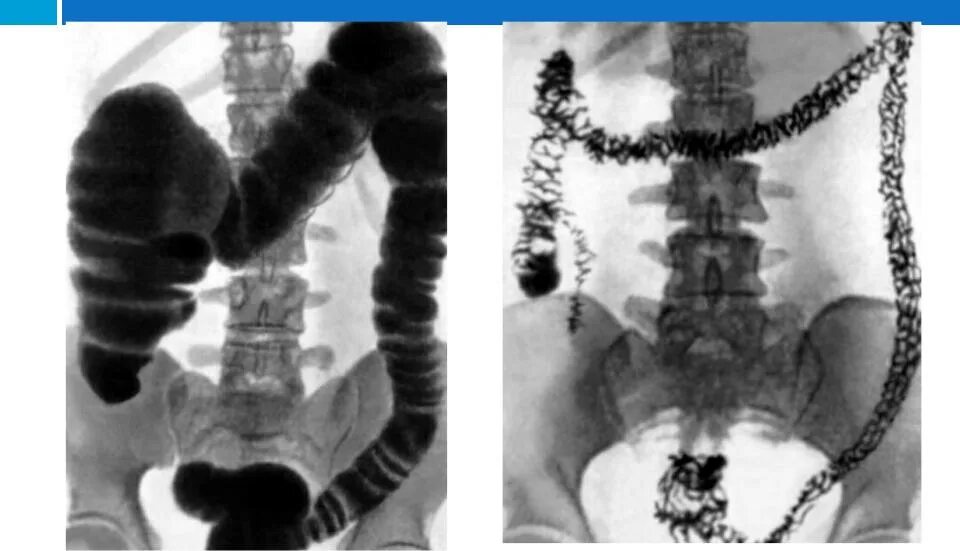

Кишечник после ирригоскопии